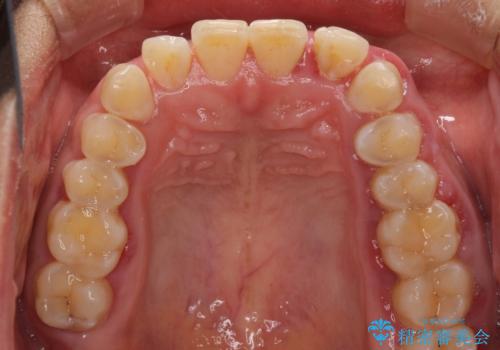

反対咬合の改善 途中で出産をしながらワイヤー矯正

- 前歯の隙間と反対咬合を気にして来院された患者様です。

咬合力が強く、反対咬合の改善に時間がかかりましたが、その後はスムーズに進めることができました。